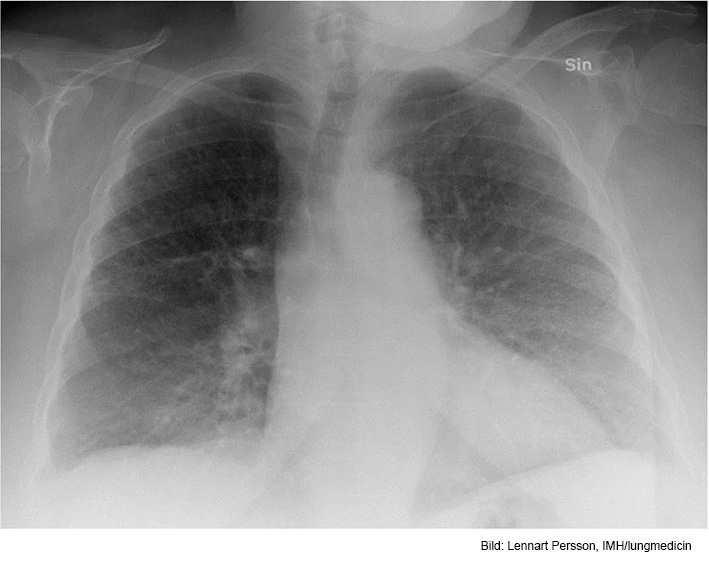

Vad ser du?

Hjärtat är allmänförstorat. Lungkärlen är vida och det finns ökad mängd pleuravätska bilateralt. Det finns spridda interstitiella och basalt på höger sida även alveolära infiltrat.

• Hjärtinkompensation.